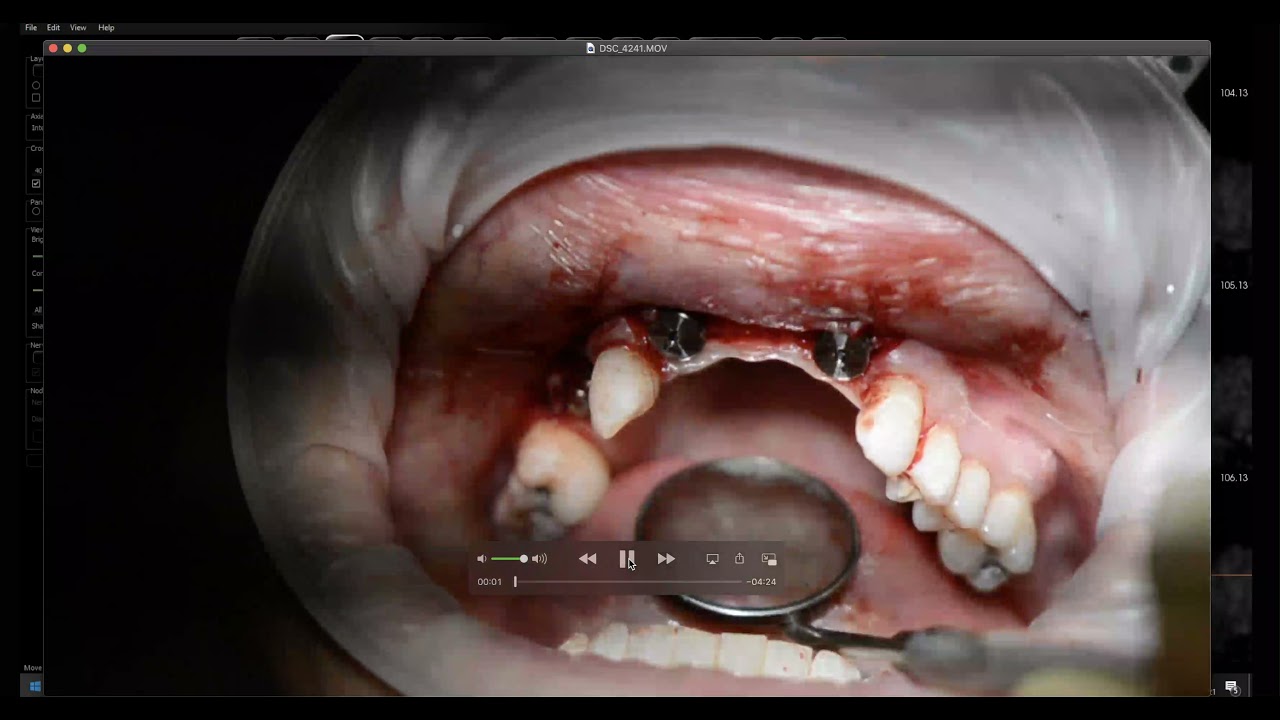

Dental Implant Surgery Periosteal Release Incision for Flap Periosteal Release The periosteal releasing incision (pri) is a commonly used technique for flap advancement. The periosteal releasing incision (pri) is very common in intraoral surgical procedures, especially when flap advancement is indicated,. Stretching the tissue may be completed by either periosteal release incisions (shallow incisions with a scalpel blade in the periosteum) or a blunt dissection (metzenbaum. The periosteal releasing incision. Periosteal Release.